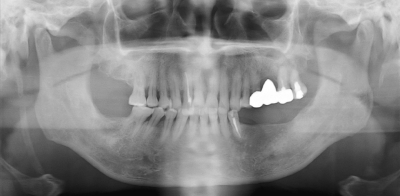

77 歳の男性。右側舌根部の疼痛を主訴として来院した。4か月前から舌を動かすと痛いという。初診時のエックス線画像を別に示す。

関連するのはどれか。1つ選べ。

a. 筋突起

b. 関節突起

c. 茎状突起

d. 乳様突起

e. 翼状突起